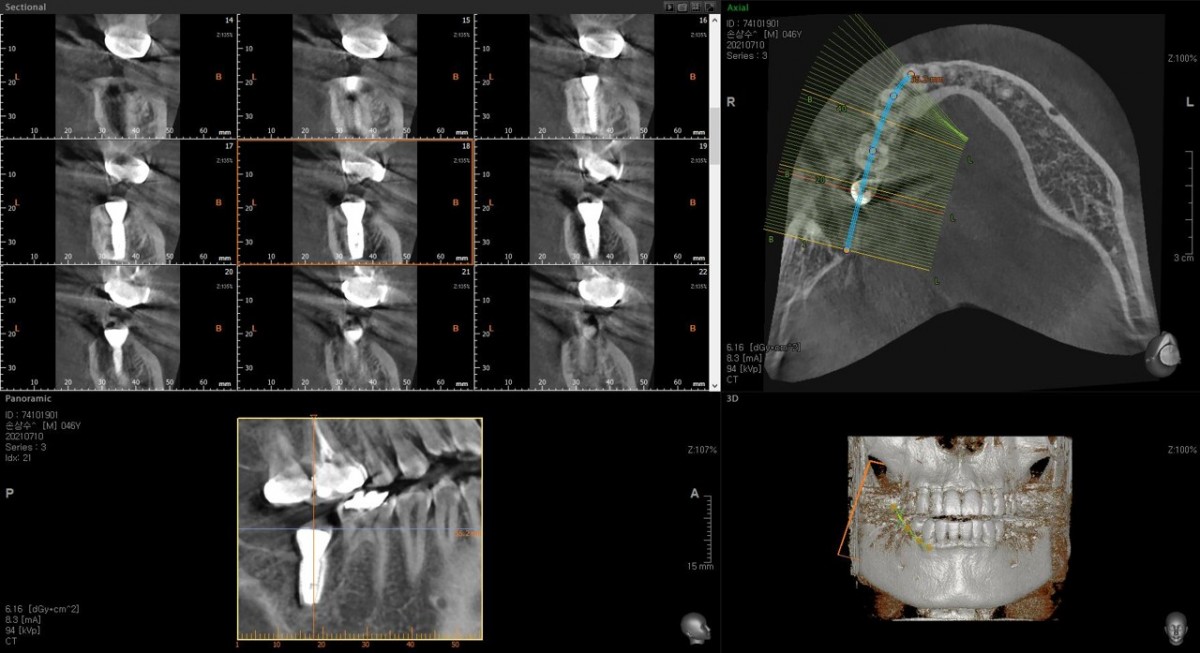

Single implant (staged) Arum NB1, f/u

A 47-year-old male patient had a crown with an ill-fitting margin and crack-tooth syndrome in the lower 2nd molar. No systemic issue.